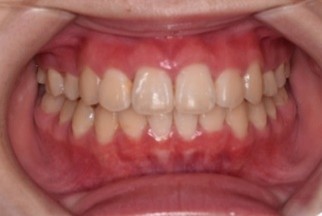

(↑マウスピース矯正後)

1~2か月毎にワイヤー矯正と同様に経過観察に来ていただきます。上の写真がマウスピース矯正後の口腔内です。きれいな歯並びになりました!